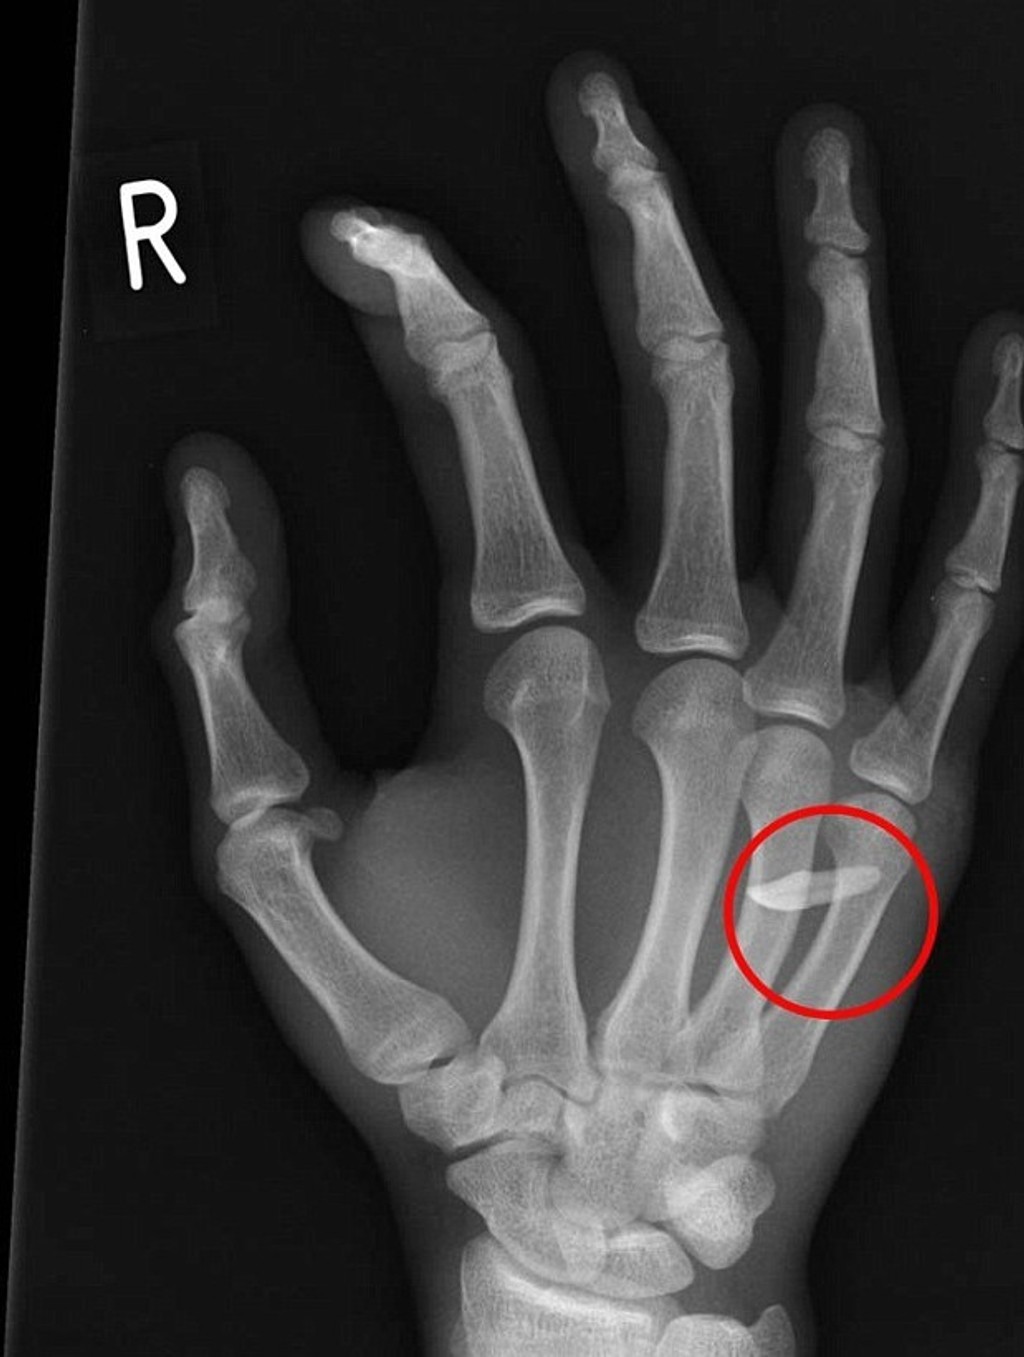

Röntgen odhalil príčinu opuchu. Mladík mal v ruke zub

Tínedžer lekárom tvrdil, že o cudzom predmete v ruke ani netušil.

Mladík prišiel do nemocnice s bolesťami a opuchnutou rukou. Röntgen odhalil, že medzi kostičkami prstov mal zub. Tínedžer lekárom tvrdil, že o cudzom predmete v ruke ani netušil.

Mladý muž (19) z britského West Sussex sa priznal doktorom, že nechtiac udrel svojho brata. Netušil však, že prišiel o zub. Brat mu mal nečakane skočiť do rany, keď doma udieral do boxovacieho vreca. Mladší súrodenec po rane tak plakal, že si ani neuvedomil, že prišiel o zub.

Ranu si mladík umyl a viac tomu nevenoval pozornosť. Až na druhý deň sa zobudil s veľkým opuchom a bolesťou. Lekári mu v nemocnici pichli tetanovku, dali antibiotiká a ranu vyčistili roztokom. Zub mu nakoniec z ruky vytiahli. Podľa denníka DailyMail sa zotavuje a nehoda mu nespôsobila žiadne následky.